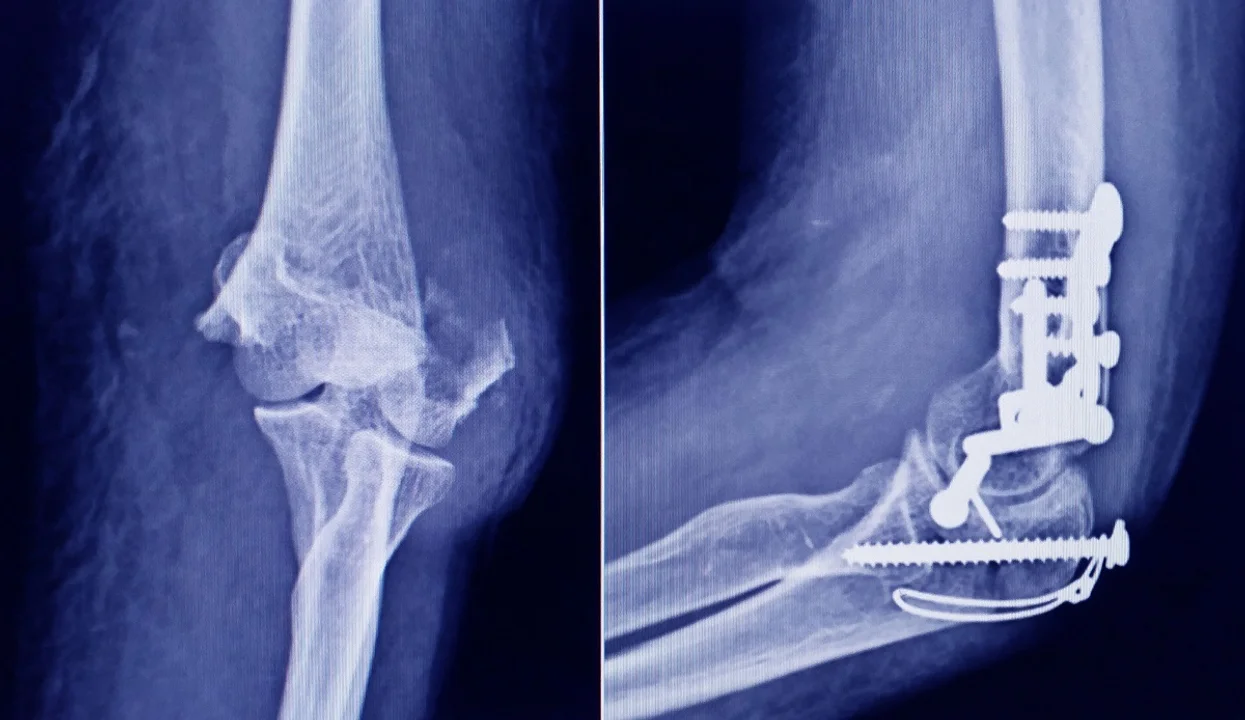

Advierten sobre un tornillo utilizado en cirugÃas traumatológicas

Su uso representa riesgo para la salud del paciente al que se lo implante.